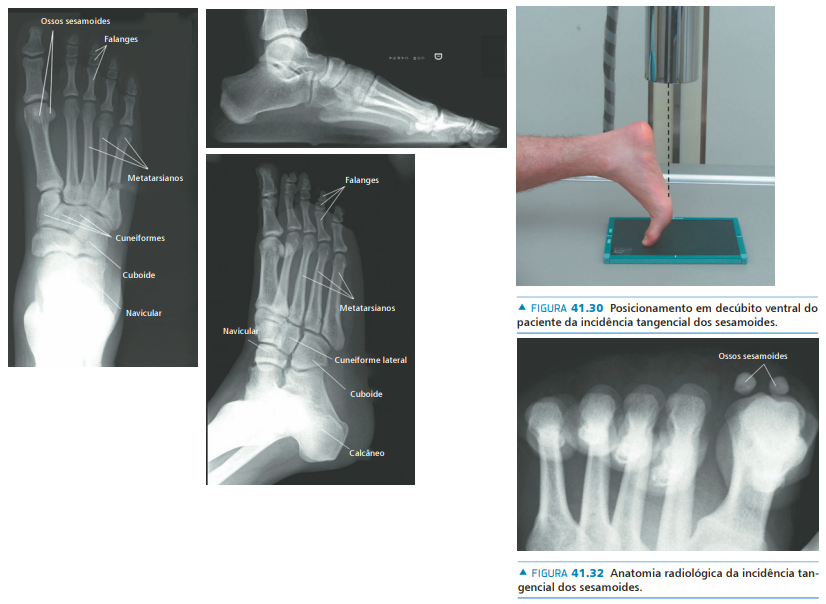

• Na avaliação radiográfica, quais incidências solicitar?

• AP com carga

• Perfil com carga

• Oblíqua

• Axial dos sesamóides